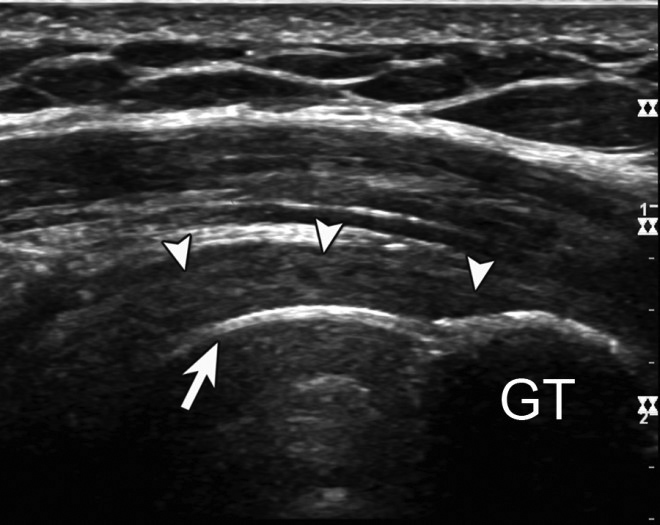

This technique can be used to evaluate for pseudotumor in metal-on-metal implants with rapid assessment of anterior, posterior, and lateral aspects of the hip to identify heterogeneous, hypoechoic masses with no or minimal intralesional vascularity on Doppler ultrasound (Figure 27) (Chen, 2011). It is also useful for evaluation of the rotator cuff in patients with prior cuff repair or proximal humerus fracture fixation (Figure 28), as well as for assessment of ankle tendons in patients with persistent pain following fracture fixation.